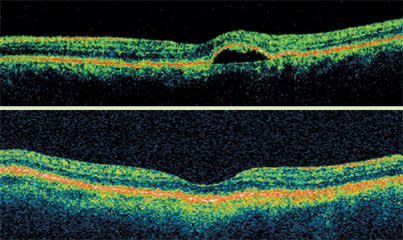

Stratus OCT high-resolution imaging is a reliable way to plan surgery for epiretinal phenomena, such as macular hole, lamellar hole or pseudohole. It clearly shows the full-thickness defect of a macular hole, the anvil-like appearance of a lamellar hole and the blunting of the reflex with a pseudohole. A pseudohole can be due to an epiretinal membrane, which is visible on OCT. Also, a sharp demarcation to the fovea is indicative of a pseudohole.

Stratus OCT images clearly show the full-thickness defect of a macular hole, the anvil-like appearance of a lamellar hole and the blunting of the reflex with a pseudohole. In contrast, on clinical observation and in red-free images, the three conditions look very similar.

Distinguishing between the three types is difficult with red-free images and clinical observation because they all tend to look as if they are full-thickness defects. Only full-thickness holes require surgery. However, surgery may be performed if an associated epiretinal membrane is present.

The Stratus OCT is useful in staging macular holes. For example, stage 1 holes are not full-thickness and usually resolve on their own. A hole that is not full-thickness but has an opening in it is a stage 2 hole. At this stage, treatment is generally peeling of the hyaloid with gas bubble.

Stage 3 holes are full-thickness. Stage 4 holes are full-thickness without the hyaloid being attached. In both cases, peeling the internal limiting membrane increases the closure rate. In some cases, whether a hole is stage 4 is not evident because the hyaloid can be outside the OCT image.